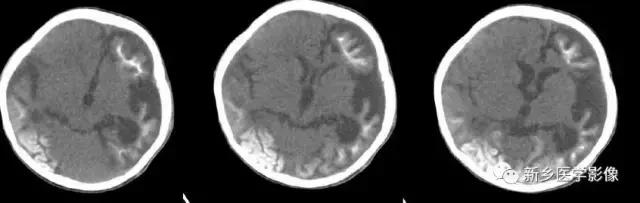

3.脑三叉神经血管瘤病

又称为脑颜面血管瘤综合征,CT平扫以一侧半球脑实质内脑回样、轨道样、弧带状或锯齿状钙化为特征。由于受累侧血供障碍,常引起脑实质萎缩.所以可以表现有患侧侧脑室扩大,颅腔变小,颅板增厚。脑内典型钙化及临床三叉伸经分布区有紫红色血管痣。